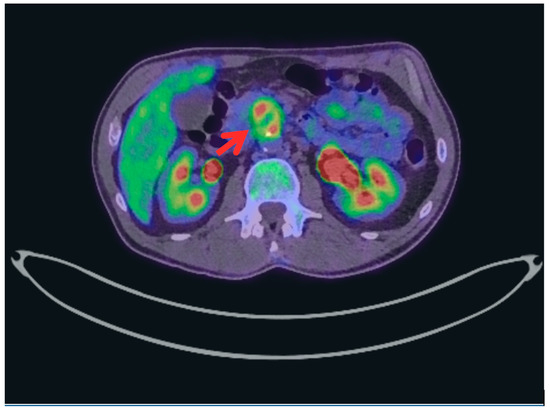

Computed tomography (CT) initially identified a non-specific lesion, which, upon review with fluorodeoxyglucose positron emission tomography (FDG-PET), was found to be a pre-aortic soft tissue mass with peripheral hypermetabolism and central hypometabolism, consistent with an inflammatory or infectious process (Figure 1). Arterial phase CT confirmed a 9 mm saccular false aneurysm from the anterior wall of the infrarenal aorta (Figure 2), with additional foci in the bilateral iliac arteries, consistent with mycotic aneurysms. Urine cultures later confirmed Mycobacterium bovis infection. The patient underwent successful endovascular stenting and anti-mycobacterial therapy, with excellent clinical improvement.

Figure 1.

Fluorodeoxyglucose Positron Emission Tomography (FDG-PET) Scan axial slice demonstrating a lesion within the infrarenal abdominal aorta with central fluorodeoxyglucose (FDG) avidity and peripheral hypometabolism, suggestive of a mycotic aneurysm.